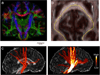

At macroscopic scales, the human connectome comprises anatomically distinct brain areas, the structural pathways connecting them and their functional interactions. Annotation of phenotypic associations with variation in the connectome and cataloging of neurophenotypes promise to transform our understanding of the human brain. In this Review, we provide a survey of magnetic resonance imaging–based measurements of functional and structural connectivity. We highlight emerging areas of development and inquiry and emphasize the importance of integrating structural and functional perspectives on brain architecture.